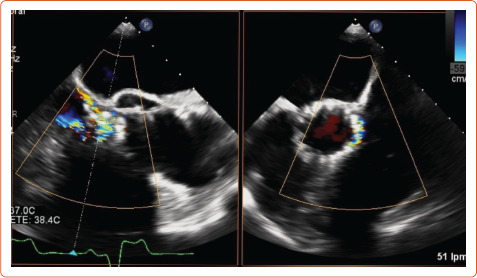

近年来,经导管主动脉瓣植入术患者发生亚临床小叶血栓形成(SLT)的现象越来越重要。CT诊断的低衰减小叶增厚和影响运动的低衰减是SLT的标志,其发生率随筛查强度而变化。这些现象是否代表小叶血栓形成,降低瓣膜耐久性和增加中风风险仍然是一个有争议的问题。TAVI后的最佳抗血栓治疗仍不确定,最佳治疗策略仍未确定。正在进行和未来的试验将为预防和治疗SLT的最佳策略提供更多证据。

In recent years, the phenomenon of subclinical leaflet thrombosis (SLT) in patients who have undergone transcatheter aortic valve implantation has become increasingly relevant. Hypo-attenuating leaflet thickening and hypo-attenuation affecting motion diagnosed by CT are the hallmarks of SLT, and their incidence varies depending on the intensity of screening. Whether these phenomena are a surrogate for leaflet thrombosis reducing valve durability and increasing the risk of stroke is still a matter of debate. Uncertainty remains over the optimal antithrombotic therapy after TAVI and the best treatment strategy is still not confirmed. Ongoing and future trials will provide more evidence about the best strategy for the prevention and treatment of SLT.